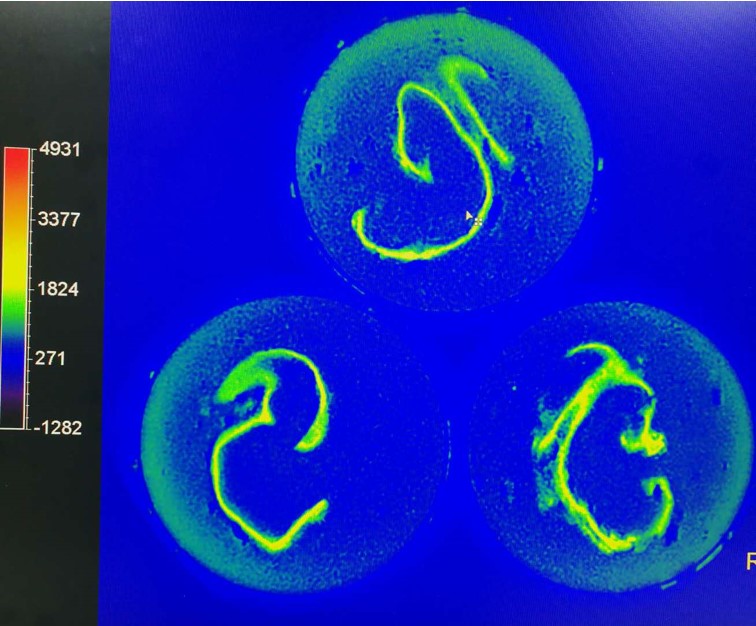

中心的研究团队包括多名医学影像领域的著名科学家和青年骨干,以医学成像和临床应用研究为核心,推动其在中国的发展,并在科技创新、产业结合方面提供多学科全球化的科研、教学和临床服务。影像中心拥有两台先进的3T全身磁共振成像系统(Philips Ingenia CX 3.0T和Siemens Prisma 3.0T),一台超高场5T全身磁共振成像系统(联影 Jupiter 5.0T),多套超声成像系统(含一台ICONEUS 脑功能超声成像系统),以及配套的成像技术、软硬件开发平台、图像数据处理工具和临床图像处理软件。中心的专业运行和技术支持团队以磁共振平台为核心,面向用户提供优秀的基础科学研究、成像技术研发和临床医学转化服务。

影像中心自成立以来,承担了科技部、国家自然科学基金委、卫生部、北京市科委等近百项国家和省部级项目,收到各种研究经费支持达5000万余元,已发表论文600余篇,发明专利60余项,国际专利10余项,培养学生130余人,获得各种奖励30余项。影像中心已成为全球重要的医学影像尤其是磁共振技术研发中心,开发出大视野高分辨血管壁多对比度成像、三维心肌定量成像、定量血流成像、定量生理成像、无变形高分辨率弥散成像等诸多原创技术,同时这些技术被广泛地应用在多项大规模临床人群队列研究当中形成了针对心脑血管、神经变性性疾病等原创性影像学解决方案。